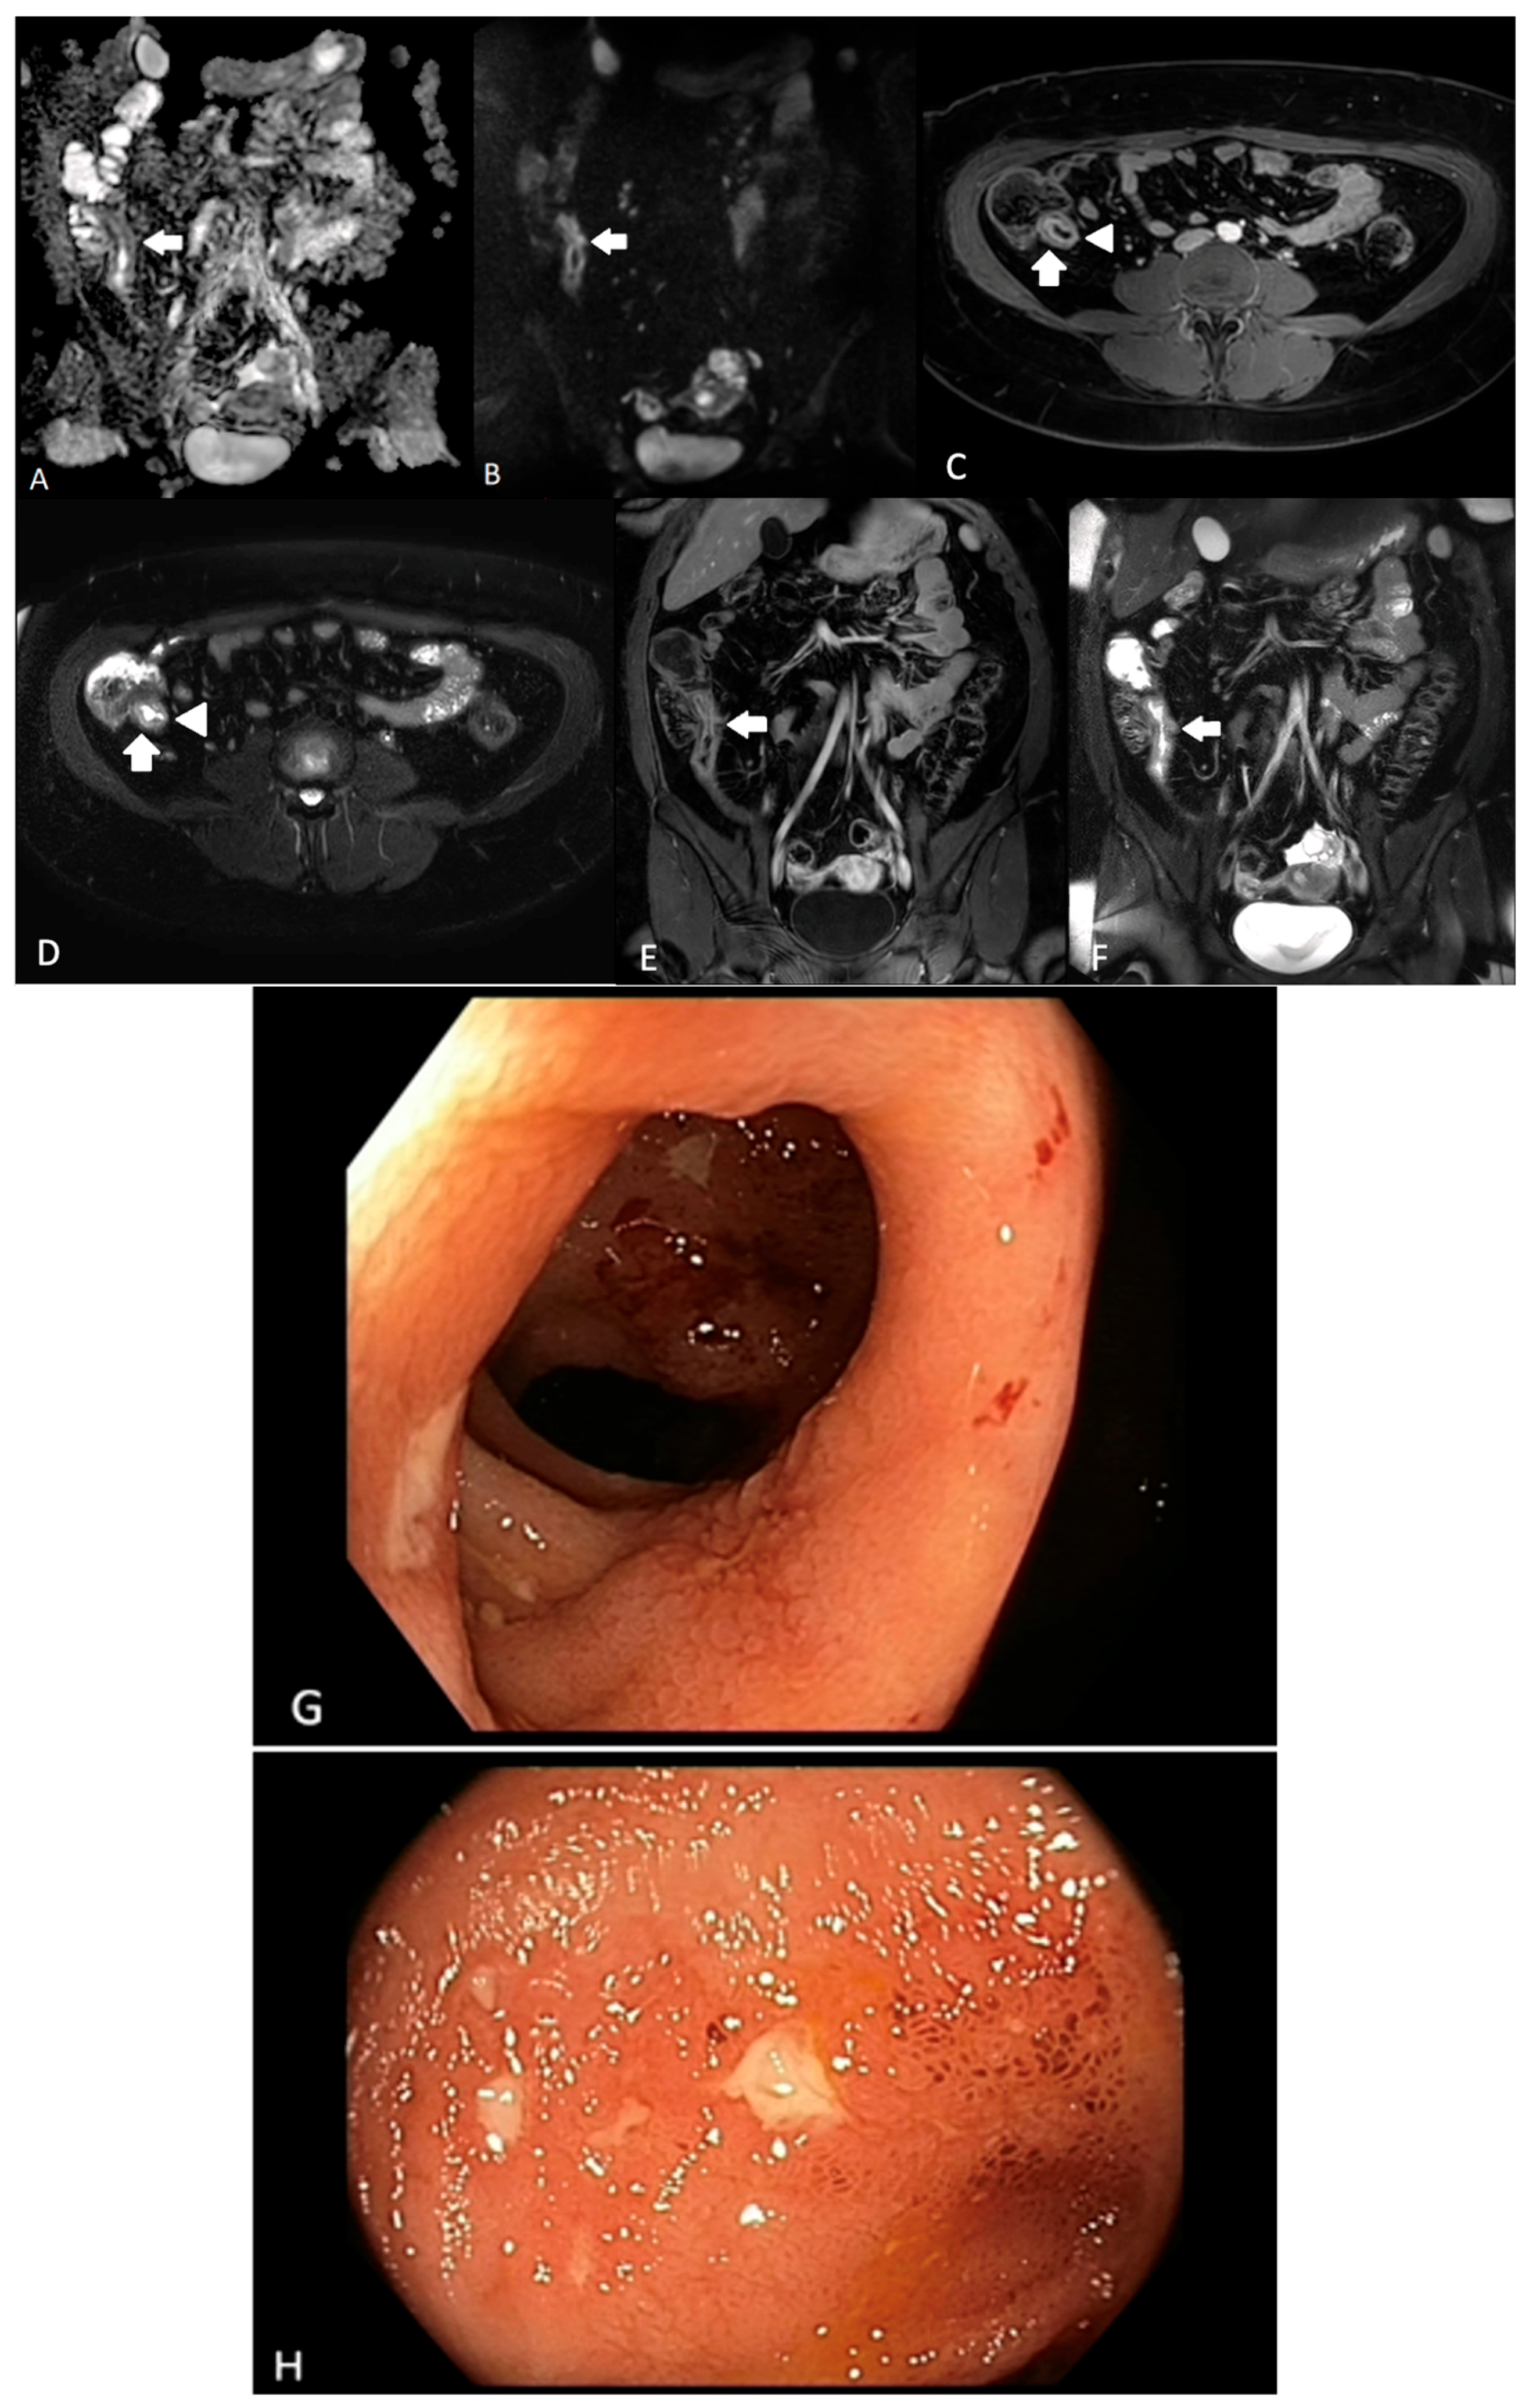

- Guglielmo, F.F.; Anupindi, S.A.; Fletcher, J.G.; Al-Hawary, M.M.; Dillman, J.R.; Grand, D.J.; Bruining, D.H.; Chatterji, M.; Darge, K.; Fidler, J.L.; et al. Small Bowel Crohn Disease at CT and MR Enterography: Imaging Atlas and Glossary of Terms. Radiographics 2020, 40, 354–375. [Google Scholar] [CrossRef] [PubMed]

- Sinha, R.; Verma, R.; Verma, S.; Rajesh, A. MR enterography of Crohn disease: Part 2, imaging and pathologic findings. AJR Am. J. Roentgenol. 2011, 197, 80–85. [Google Scholar] [CrossRef]

- Rimola, J.E. Cross-Sectional Imaging in Crohn’s Disease, 1st ed.; Springer International Publishing: Cham, Switzerland, 2019. [Google Scholar]